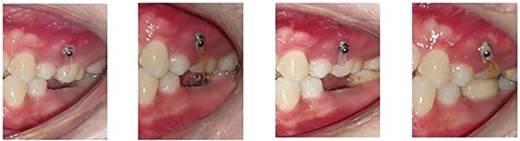

Following the placement of miniscrews, immediate loading was done with 100 g of intrusive force using a short power chain. The power chain was passed and engaged onto the composite button to ensure the forces are directed occlusally and there is no slippage. The patient was followed up at 4-week intervals and the power chain was replaced with one link, which was reduced at each appointment. After the first month, the dental implant was placed to replace the mandibular first molar. After 5 months of intrusion, the desired occlusal clearance was achieved and the upper and lower impressions were recorded (Fig. 2). For retention in the upper arch, the patient was given a clear vacuum retainer, while the crown was placed on the implant to prevent any relapse and to achieve good occlusion.

The intrusion process with placement of the prosthetic crown at the completion stage.